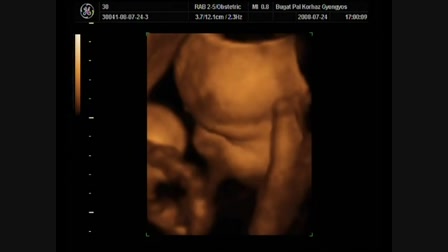

Levi produkál!